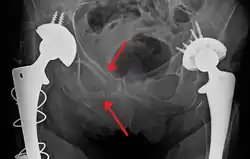

Pelvic fracture

Pelvic vertical shear fracture

Fractures of the superior (in two places) and inferior pubic rami on the person's right, in a person who has had prior hip replacements